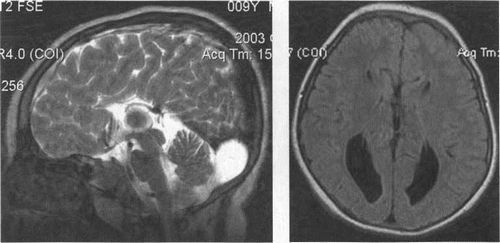

3.9. Агенезія мозолистого тіла. а - Т2-ВІ, сагітальній площині,

б - FLAIR ІП, аксіальна площина, в - в режимі Т1, корональна площину.

Мозолисте тіло відсутня. На його місці візуалізуються внутрішні і велика вени. Бічні шлуночки широко розставлені, задні роги бокових шлуночків диспропорційно розширені, передні роги вузькі, щілиновидні. Контури задніх рогів бічних шлуночків хвилясті. Виявляється ретроцебеллярная кіста.